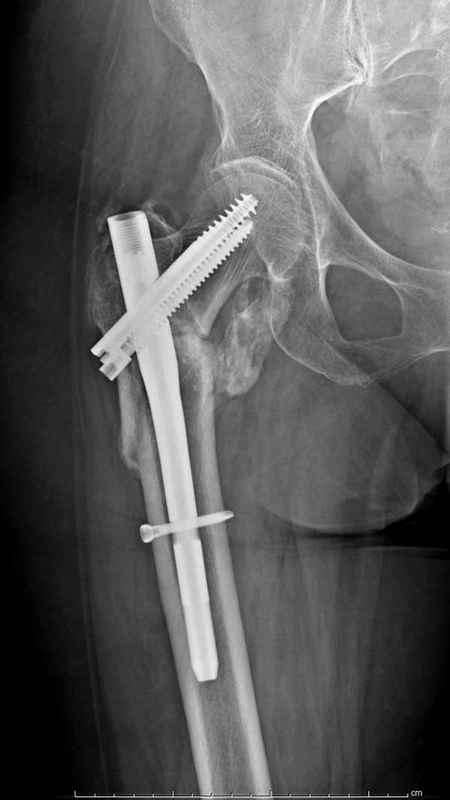

Из фиксаторов, мы бы применили цефаломедуллярные, потому что они "по закону моментов" из-за короткого рычага от центра головки к диафизу и по принципу "головка диафиз" механически лучше выдерживают нагрузки, чем пластины.

Здесь пара случаев фиксации похожих переломов:

первый высокоэнергетическая травма 36 лет